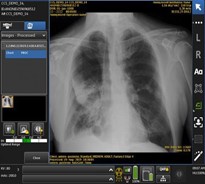

L’avenir, c’est aujourd’hui : sommes-nous à la veille de livrer la technologie de l’IA comme solution aux problèmes du monde réel qui existent au Québec et au Canada? McGill a récemment fait une annonce au sujet d’un cas d’utilisation de l’IA dans le monde réel pour soutenir l’accès à des soins de santé de meilleure qualité pour les collectivités rurales. Piloté par le Dr Reza Forghani, M.D., PhD, chef adjoint du département de Radiologie de l’Hôpital général juif, et la Dre Caroline Reinhold, M.D., MSc, professeure et directrice adjointe de recherche du Centre universitaire de santé McGill, le projet fera appel à l’IA pour analyser les images médicales d’urgence qui doivent être examinées en priorité afin de prodiguer des soins plus rapidement et potentiellement sauver des vies. Cette nouvelle technologie sera surtout utilisée pour les radiographies et les tomodensitogrammes, qui sont les pierres angulaires du diagnostic et de l’imagerie médicale d’urgence.

Critical Care Suite

La technologie en matière de radiographie s’est améliorée avec le numérique et plus récemment avec la haute définition. La prochaine étape est d’embarquer l’IA afin de non seulement améliorer la qualité d’image et fournir des informations cliniques au point d’intervention, mais aussi d’assister le radiologiste dans son diagnostic en lui fournissant des renseignements cruciaux. GE Santé a intégré directement et en position adjacente des technologies avancées sur les dispositifs pour améliorer la qualité d’image et le diagnostic tout en réduisant le rejet ou la répétition d’images.

Critical Care Suite: en septembre 2020, Santé Canada a autorisé le premier algorithme d’IA embarqué sur un dispositif médical pour prioriser les radiographies thoraciques critiques appelé la suite des soins intensifs (de l’anglais « Critical Care Suitemc »). Cette solution a été développée en collaboration avec l’hôpital Humber River au Canada; elle met en valeur une série d’algorithmes d’IA intégrés dans les systèmes de radiographie qui servent à effectuer des mesures automatiques, à prioriser les cas et à contrôler la qualité. La Critical Care Suitemc est une collection encore jamais vue d’algorithmes d’IA intégrés dans le dispositif de radiographie mobile Optimamc XR240amx de GE Santé. L’IA embarquée analyse automatiquement les images sur dispositif et signale les cas de pneumothorax suspectés pour produire de manière fiable et rapide les résultats de l’IA générés dans les secondes qui suivent l’acquisition des images. Ce processus s’exécute indépendamment de la vitesse de connexion ou de transfert pour produire les résultats de l’IA qui sont envoyés au radiologiste pendant que le dispositif partage simultanément les images diagnostiques originales de manière à ne pas retarder le processus. La Critical Care Suite a été mise au point de manière optimale grâce au solide partenariat entre GE Healthcare et Intel® au moyen de leur solution OpenVinomc.